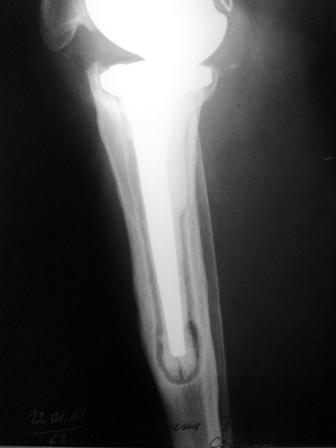

Хотелось бы услышать Ваше мнение о возможности и способе помощи

больной. 1939 г.р. В 1995г. эндопротезирование правого коленного

сустава протезом Феникс, в 1999г. в г. Томске - ревизия - ротационный

хинч W.Link. C 2005г. прогрессирует варусная деформация за счет

нестабильности тибиального компонента. Попытка ортезирования - без